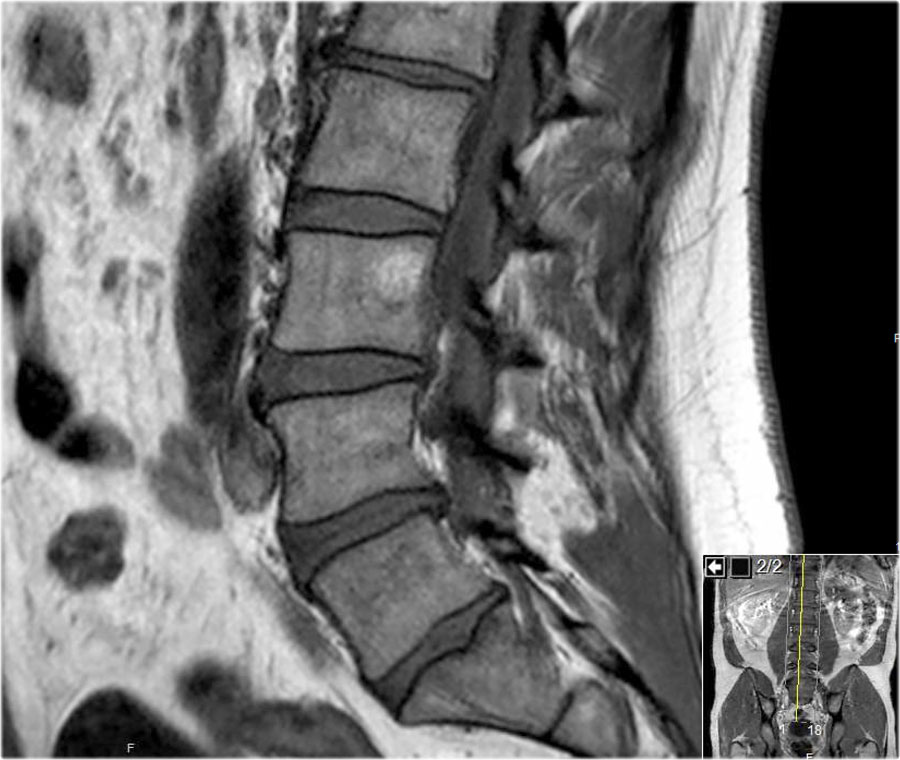

Các hình ảnh cắt dọc chuỗi xung T1W cung cấp nhiều thông tin chẩn đoán nhất.

Trước khi bắt đầu tìm kiếm bất kỳ thoát vị nào, hãy quan sát kỹ các mô trước cột sống và tủy xương.

Khi đã phát hiện bất thường, hãy đối chiếu các phát hiện này với hình ảnh chuỗi xung T2W (hình).

Các dấu hiệu tại các mức 1-4 như sau:

- Tại mức đĩa đệm, có hẹp ống sống tối thiểu do phình đĩa đệm và thoái hóa khớp mỏm khớp.

- Tại mức này, có hẹp ống sống nặng do phình đĩa đệm và thoái hóa khớp mỏm khớp.

Ngoài ra còn có rách vòng sợi (tăng tín hiệu) là nơi đĩa đệm thoát vị qua (mũi tên vàng). - Tại mức ngách bên, có thoát vị khu trú của chất đĩa đệm gây chèn ép rễ thần kinh L5 (mũi tên vàng).

Đây được gọi là thoát vị thực sự (extrusion), vì khoảng cách giữa các bờ của khối thoát vị lớn hơn khoảng cách tại nền. - Rễ thần kinh L5 bị chèn ép (mũi tên xanh dương) trong ngách bên.

Đĩa đệm thoát vị đã di trú xuống phía dưới và được thấy như một cấu trúc hình bầu dục nằm phía trước rễ thần kinh.

Đĩa đệm thoát vị không được bao bọc, tức là không được che phủ bởi các sợi của vòng sợi.